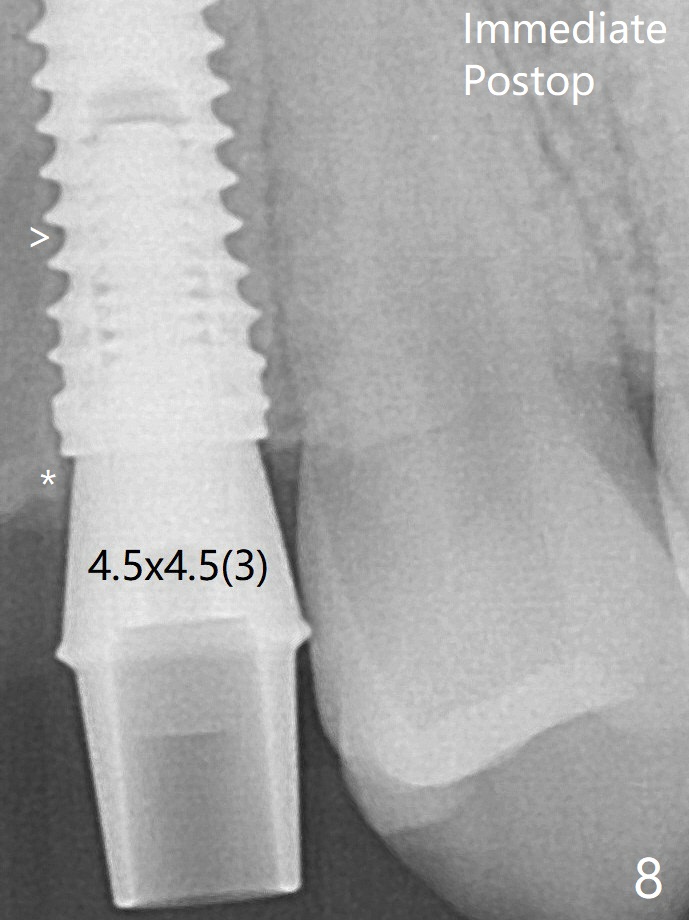

术后4个月牙槽嵴(图八:*)吸收(图十一:^),刚植入时的间隙(图八:>)四个月后仿佛消失。